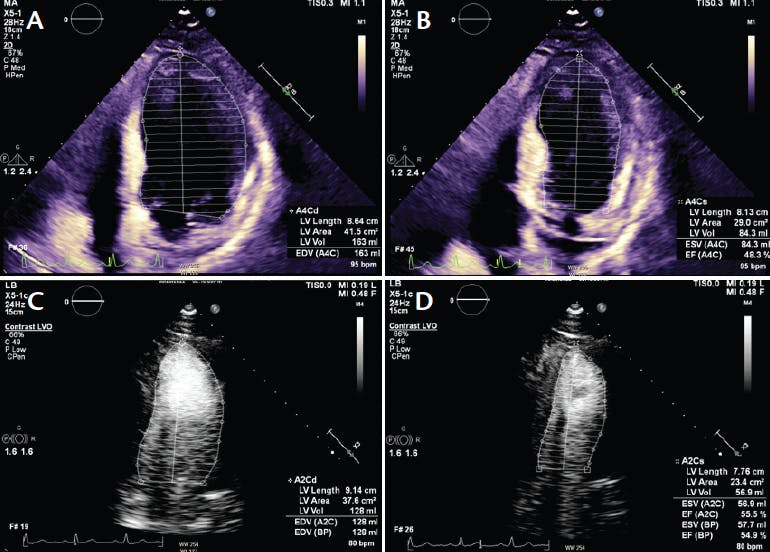

At approximately 30 minutes into the SSO2 infusion, TTE was performed with Definity contrast (Lantheus) by an expert cardiac sonographer (Videos 1-4). A remarkable improvement in global and regional systolic left ventricular (LV) function (compared to the pre–left-heart catheterization TTE and post-PCI LV image) was noted, with an LVEF of 45% and only mild to moderate apical hypokinesis. Repeat TTE at day 1 was similar but with a slightly lower LVEF (40%), despite the > 50-ng/mL troponin. Stenting of the left circumflex stenosis was successful on day 2. The patient was discharged on day 4 without complication and near normalization of the 12-lead ECG. Follow-up TTE at 1 month (Figure 1) showed an LVEF of 40% and at 2.5 months a further improvement in LVEF to approximately 50% to 55%.

Figure 1. TTE performed at 1 month (A, B) and 2.5 months after SSO2 therapy (C, D).

The magnitude of recovery of LV function between 2 days and 3 months in all anterior SSO2 patients treated at our institution (n > 24), including this patient, has been robust, with at least a 20% absolute increase in LVEF. Remarkably, in this case, we observed a dramatic acute improvement of LV function (as demonstrated by improved contractility) during SSO2 therapy, suggesting an immediate reversal of obstructive microcirculatory responses associated with reperfusion microvascular ischemia. Not only did our patient have a rapid improvement in LVEF during SSO2 therapy, echocardiography showed LV function normalized by 2.5 months after the procedure.

CONCLUSION

The remarkably rapid LV improvement noted by TTE contrast at 30 minutes of SSO2 infusion suggests the following: (1) SSO2 therapy should be considered a hemodynamically important interventional adjunct in STEMI patients; (2) physiologic mechanisms for acute edema removal, as demonstrated by hyperbaric oxygen therapy studies,1,2 are relevant for SSO2, with improved LV contractility further reducing edema and improving red cell flow through injured capillaries; and (3) the acute SSO2 contrast TTE results likely predict long-term LV recovery.